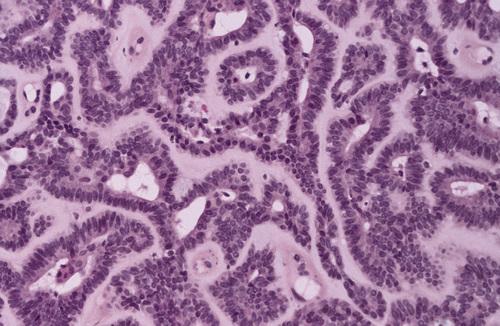

Uniform columnar cells forming canal-like ductal structures. The microscopic pattern of this tumor is monomorphic in nature.

canalicular adenoma